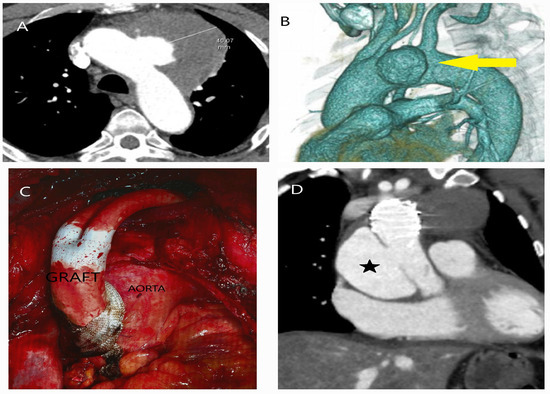

5.2.3. Computed Tomography

- Evangelista, A.; Sitges, M.; Jondeau, G.; Nijveldt, R.; Pepi, M.; Cuellar, H.; Pontone, G.; Bossone, E.; Groenink, M.; Dweck, M.R.; et al. Multimodality imaging in thoracic aortic diseases: A clinical consensus statement from the European Association of Cardiovascular Imaging and the European Society of Cardiology working group on aorta and peripheral vascular diseases. Eur. Heart J. Cardiovasc. Imaging 2023, 24, e65–e85. [Google Scholar] [CrossRef] [PubMed]

- Bossone, E.; Czerny, M.; Lerakis, S.; Rodríguez-Palomares, J.; Kukar, N.; Ranieri, B.; Russo, V.; Punzo, B.; Cocchia, R.; Cademartiri, F.; et al. Imaging and Biomarkers in Acute Aortic Syndromes: Diagnostic and Prognostic Implications. Curr. Probl. Cardiol. 2021, 46, 100654. [Google Scholar] [CrossRef]

- Sathiadoss, P.; Haroon, M.; Wongwaisayawan, S.; Krishna, S.; Sheikh, A.M. Multidetector Computed Tomography in Traumatic and Nontraumatic Aortic Emergencies: Emphasis on Acute Aortic Syndromes. Can. Assoc. Radiol. J. 2020, 71, 322–334. [Google Scholar] [CrossRef] [PubMed]